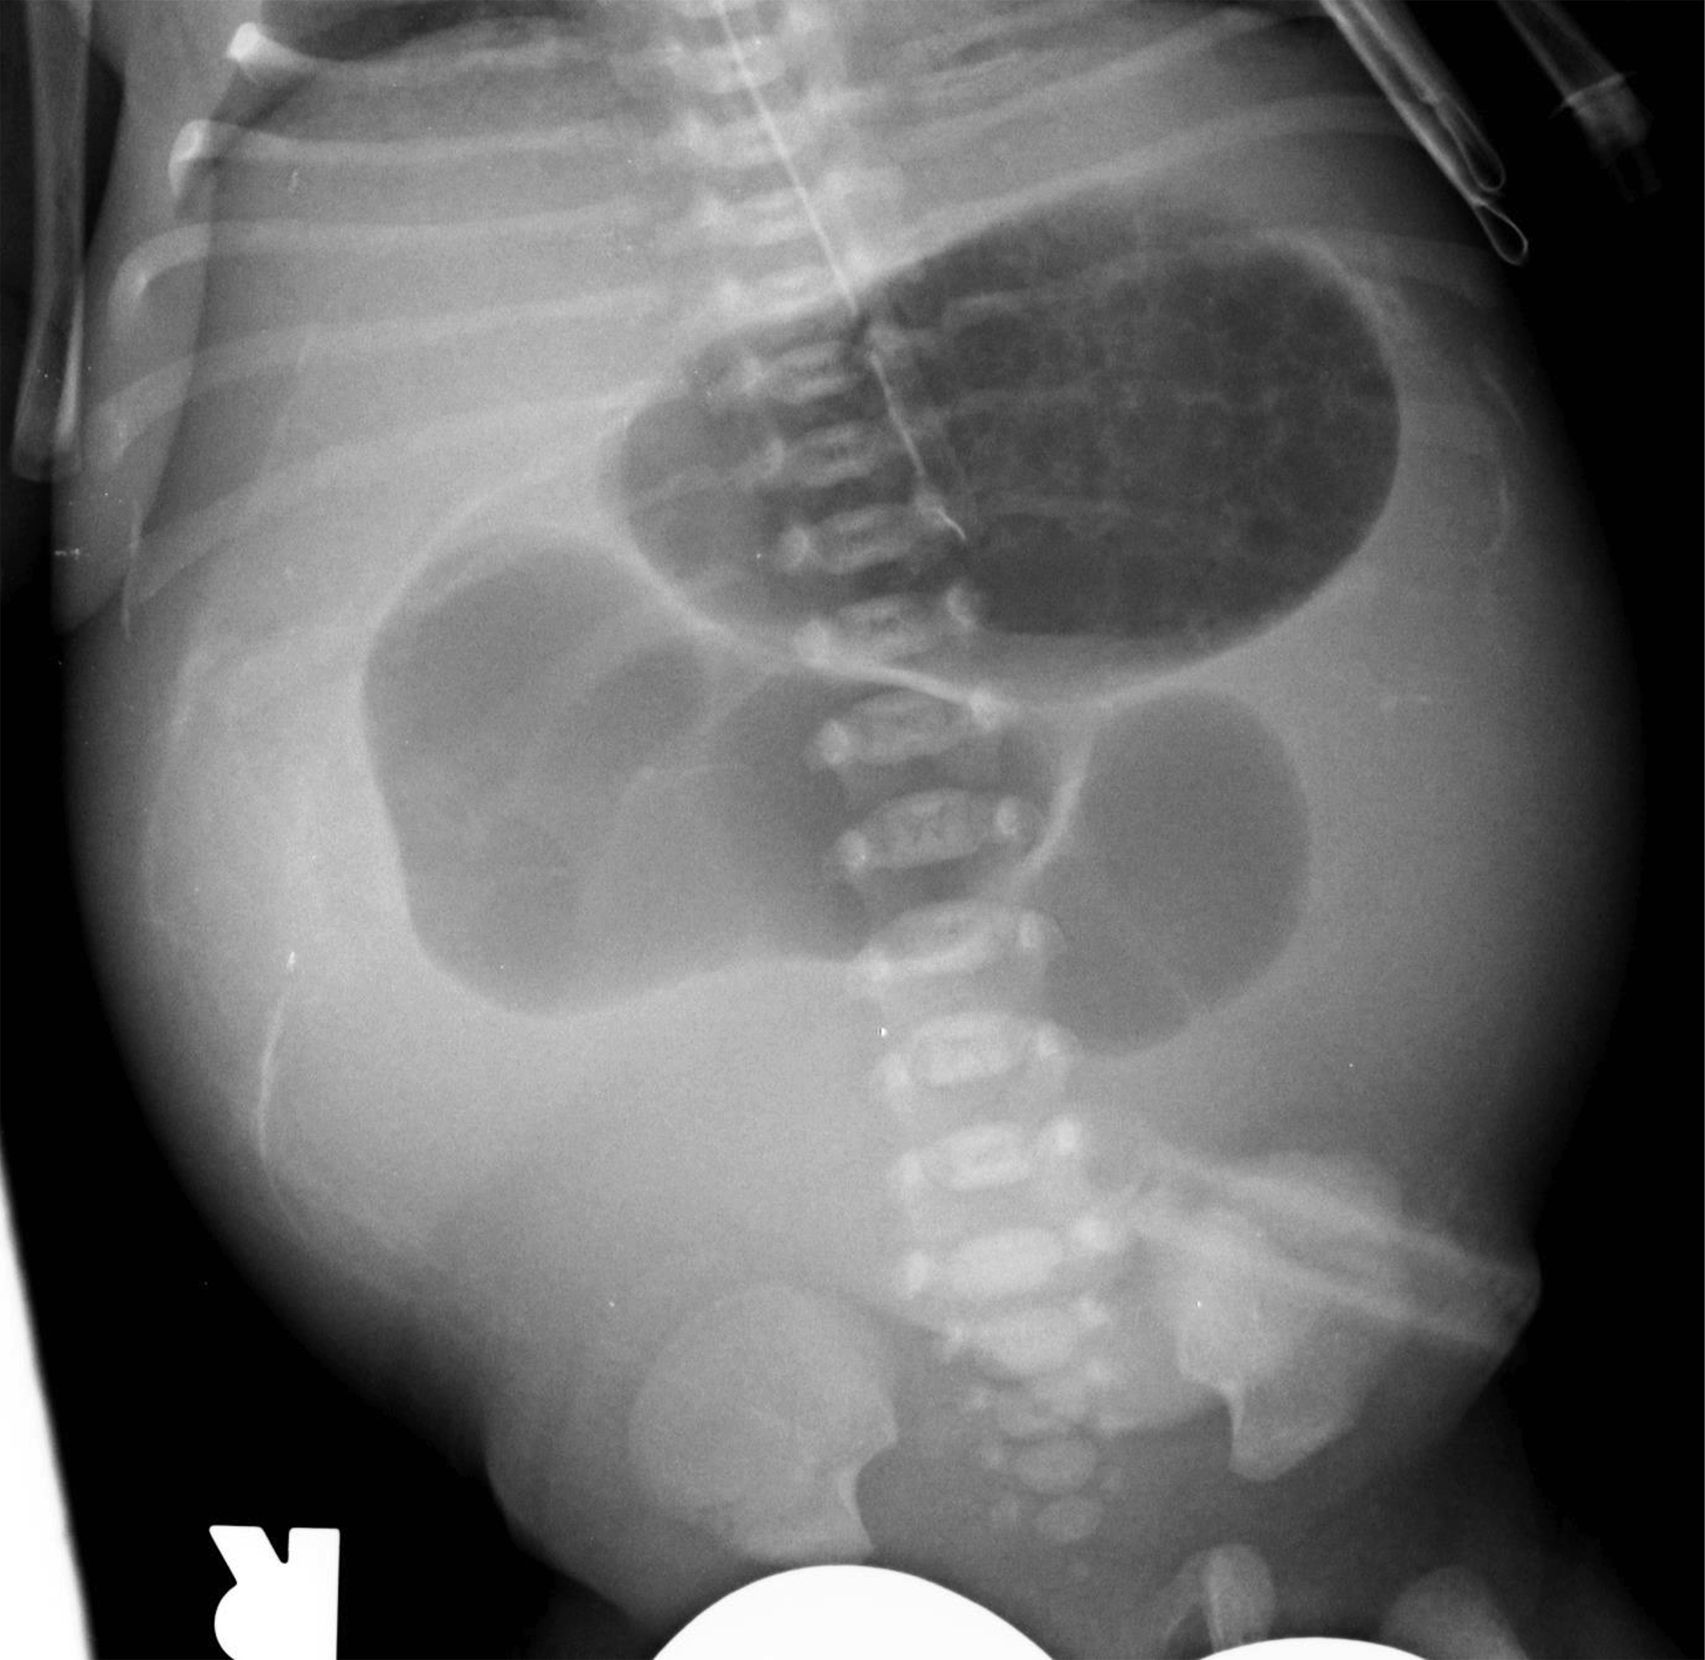

Jejunal and ileal atresias comprise half of all intestinal atresias; colonic atresia is less common, accounting for only 9% of atresias. These atresias may be associated with abnormalities in other organ systems. Unlike duodenal atresia, which is caused by a failure of recanalization of the bowel lumen, distal atresias are thought to result from in utero vascular accidents. Multiple foci of bowel atresia may occur in one patient. Proximal small bowel detritus forms meconium; thus in jejunal atresia the infant may pass meconium, whereas with ileal or colonic atresia meconium will not be passed. Radiographs in jejunal atresia typically show dilatation of the stomach, duodenum, and one or a few loops of additional bowel ( Fig. 4.10 ); there may be a “triple-bubble” appearance. In more distal atresias, multiple dilated loops of bowel are more commonly seen ( Figs. 4.11 and 4.12 ). Regardless, further workup is performed with contrast enema to locate the level of the obstruction. The more distal the atresia location, the more “unused” the colon is, often resulting in a “microcolon” appearance on enema.

Fig. 4.11, Ileal atresia.